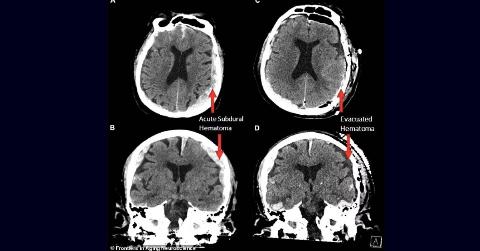

Pictured are CT scans of the patient, whose identity was not disclosed. Spirituality Brain Activity Of Dying 87 Y.O Man Suggests Our Lives Really Do Flash Before Our Eyes